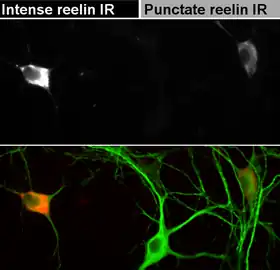

Having peaked just after the birth, the synthesis of reelin subsequently goes down sharply, becoming more diffuse compared with the distinctly laminar expression in the developing brain. In the adult brain, reelin is expressed by GABA-ergic interneurons of the cortex and glutamatergic cerebellar neurons,[33] the glutamatergic stellate cells and fan cells in the superficial entorhinal cortex that are supposed to carry a role in encoding new episodic memories,[34] and by the few extant Cajal-Retzius cells. Among GABAergic interneurons, reelin seems to be detected predominantly in those expressing calretinin and calbindin, like bitufted, horizontal, and Martinotti cells, but not parvalbumin-expressing cells, like chandelier or basket neurons.[35][36] In the white matter, a minute proportion of interstitial neurons has also been found to stain positive for reelin expression.[37]

Reduced expression of reelin and its mRNA levels in the brains of schizophrenia sufferers had been reported in 1998[115] and 2000,[116] and independently confirmed in postmortem studies of the hippocampus,[12] cerebellum,[117] basal ganglia,[118] and cerebral cortex.[119][120] The reduction may reach up to 50% in some brain regions and is coupled with reduced expression of GAD-67 enzyme,[117] which catalyses the transition of glutamate to GABA. Blood levels of reelin and its isoforms are also altered in schizophrenia, along with mood disorders, according to one study.[121] Reduced reelin mRNA prefrontal expression in schizophrenia was found to be the most statistically relevant disturbance found in the multicenter study conducted in 14 separate laboratories in 2001 by Stanley Foundation Neuropathology Consortium.[122]